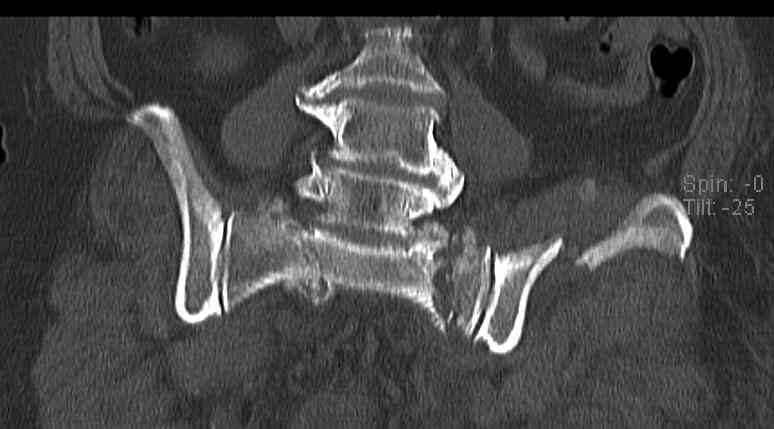

Уважаемые коллеги, в продолжение обсуждения перелома костей таза с отрывами остей досылаю R-снимки (КТ и КТ с 3d реконструкцией)